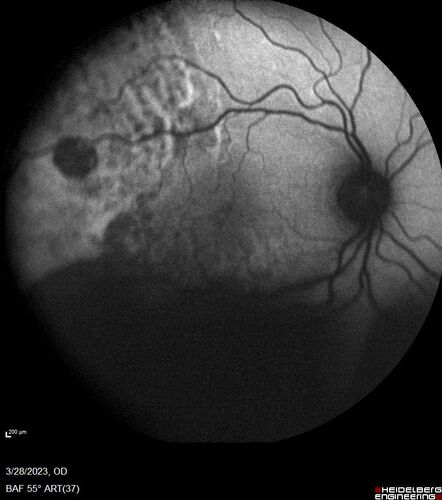

Choroidal Metastatic Breast Cancer with Exudative Detachment

58 year old female presented with 20/200 vision. Had 10 sessions of radiation and tumor shrank. The exudative detachment took almost a year to resolve. The vision improved to 20/40.